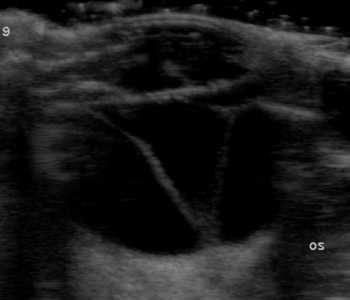

【超音波(エコー)検査】

目の中、特に硝子体や網膜など水晶体の裏側がどのような状態なのか調べます。エコー検査により、白内障の混濁状態や網膜剥離や眼内出血などの合併症の評価を行います。

網膜剥離